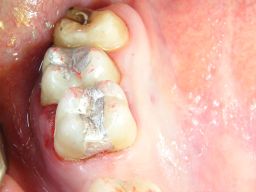

Mittelgroße und große Amalgamfüllung

Warum heute noch Amalgam? Weil die im Preis vergleichbaren (Zuzahlung bei mir je nach Größe ca. 30, 40, 55 oder 68 €), weißen Kunststofffüllungen (Komposit) trotz neuesten Materials und aufwendiger Verarbeitung die Haltbarkeit und Sicherheit von Amalgam noch nicht erreichen, wie umfangreiche Literaturübersichten gezeigt haben (1, 2, 3). Das gilt für den besonders kaubelasteten Seitenzahnbereich. Hier kommt es bei tiefen Kunststofffüllungen auch 4mal häufiger zum Absterben des Zahnnerven als mit Amalgam.